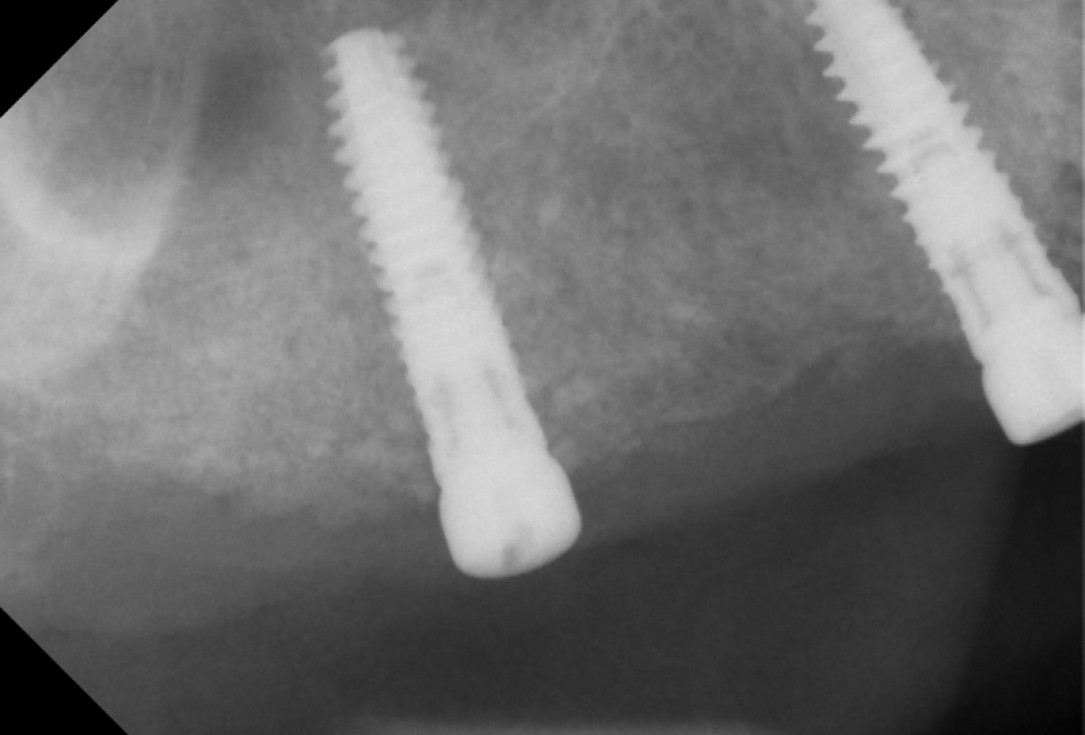

01/13 - DVT image demonstrating horizontal and vertical amount of bone available

Sinus lift with simultaneous bone splitting & implantation - Dr. F. Kistler